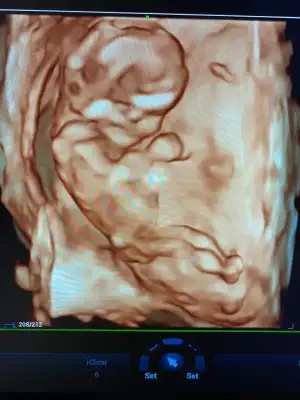

İnşallah dediğiniz gibi olur kızlar ama hiç zannetmiyorum benim 2 kızımada devlette 12 haftada kız dediler değişmedi, bugün özeldeydik renkli renksiz bütün usg lere baktı yarım saat inceledi neredeyse, pozisyonuda uygundu bacak arası boştu ben biile gördüm, ben değişceğini düşünmüyorum kız olduğunu kabullendim hayırlısı böleymiş 😍😍😍

• IMG-20210504-WA0021.webp

IMG-20210504-WA0021.webp

40 KB · Görüntüleme: 70

Ya doktor zaten dediki ben normLde 14 haftdan önce kesinbelli olmadan cinsiyet söylemiyorum, ama ben başından beri aynı doktora gidiyorumya biliyor mevzuları erkek istediğimi upraştıpımı filan bugün o benden meraklıydı yani düşün, o yüzden çok inceledi yani o yine kesin değil amabacak arası boş dedi sadece3 hafta sora gel netkeşir kesin kız diyemem dedi, amaarkadaşım 11 +3 tü cuma günü erkek dedi ona doktor yani ben bugün 12+6 bu kadarda gelişmiş ultrasyonda bide öle yakınlaştırdıki o demeden ben gördüm hemen dedim oğlan olaydı en azından bi ufak çıkıntı olurdu diye, çünkü bacak arasını net gördük, benim için mucize öyle birşey olmayacak değişmiyecekte yinede inş diyeyim 🤲🤲